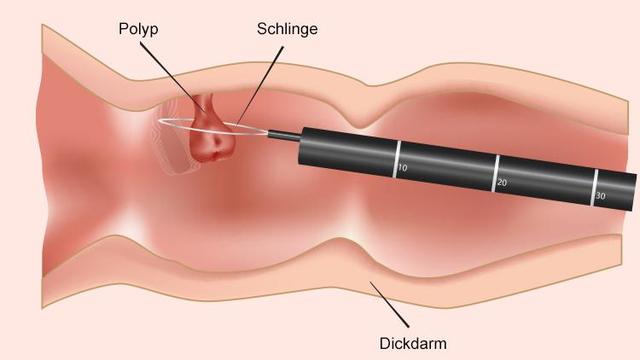

– Für die Untersuchungsdauer ca. eine halbe bis 1 Stunde einplanen, durch Polypenabtragungen oder technisch schwierige Untersuchungen kann jedoch mehr Zeit nötig sein.

– Die Untersuchung dauert in der Regel etwa eine halbe bis 1 Stunde, es kann jedoch länger dauern, wenn beispielsweise Polypen entfernt werden müssen.